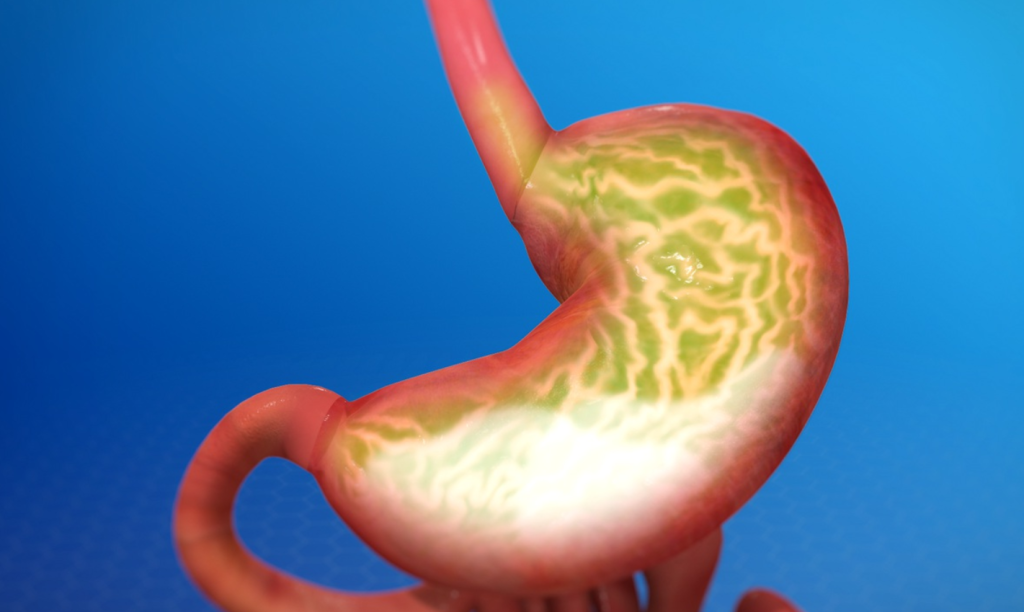

🔥 ما هو ارتجاع الحمض؟

ارتجاع الحمض (GER) هو تدفّق محتويات المعدة الحمضية إلى المريء. إذا تكررت الحالة بشكل مزمن، قد تؤدي إلى مرض الارتجاع المعدي المريئي (GERD)، وتظهر الأعراض مثل حرقة المعدة، التجشؤ، وصعوبة البلع.